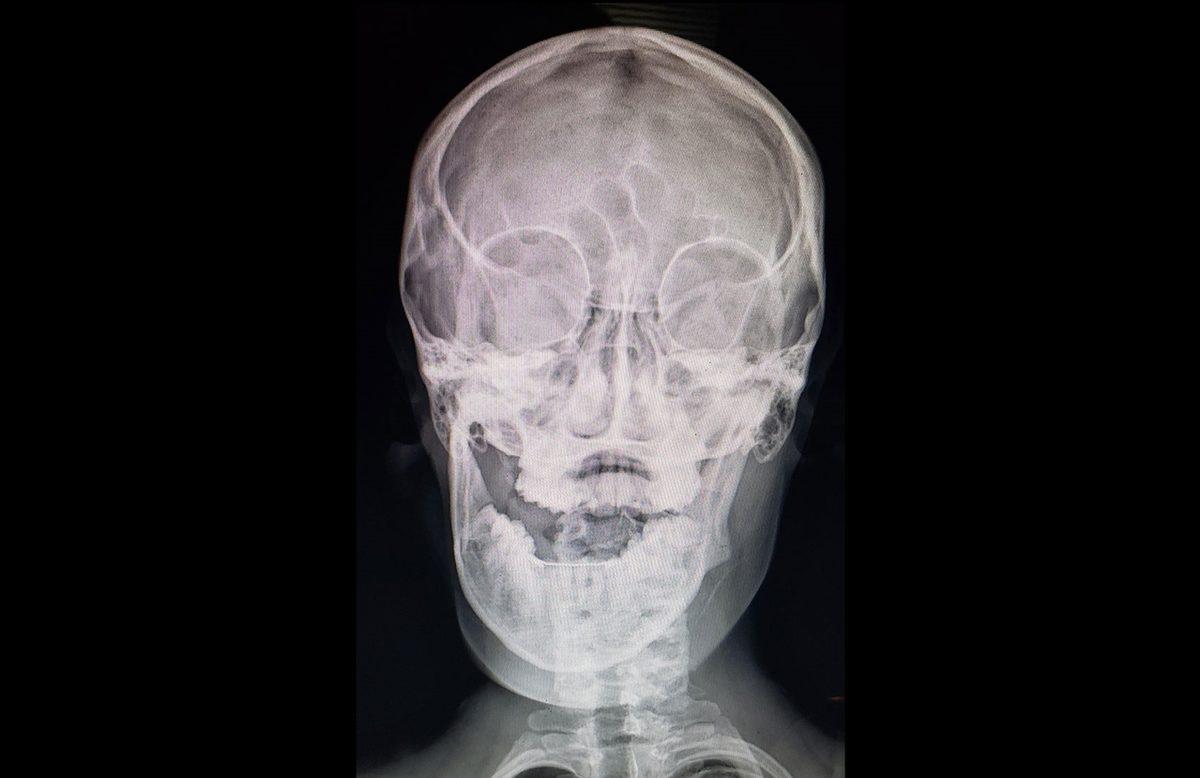

- "Mısır gevreği yerken" çenesi çıkan biri.